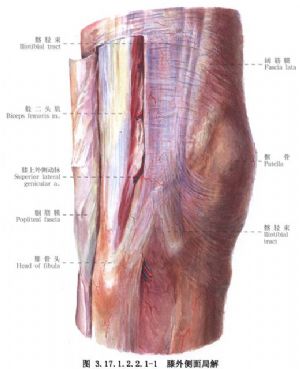

手術相關解剖見下圖(圖3.17.1.2.2.1-1,3.17.1.2.2.1-2)。